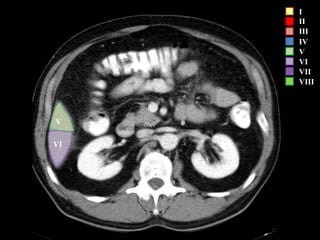

I – Entre cava y porta

II – el más superior de los izquierdos

III – Por debajo del II

IV – por delante de la vesícula

V – por detrás de la vesícula

VI – relación con riñón derecho

VII – el más posterior de los segmentos superiores

VIII – domo hepático

Las claves de la segm. Hepática